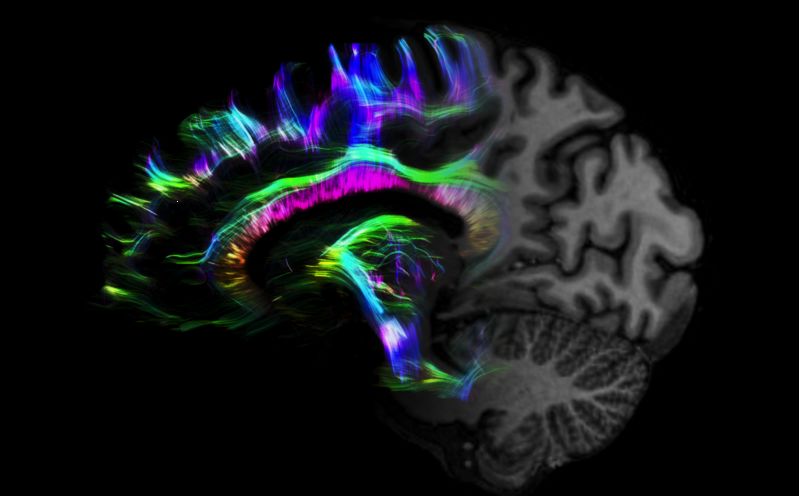

MAGNETOM Terra在業(yè)界首次實(shí)現(xiàn)了兩倍于傳統(tǒng)7T的超強(qiáng)梯度性能,實(shí)現(xiàn)超快速、超高效、超高分辨功能磁共振成像。如此高性能的梯度系統(tǒng)無(wú)論對(duì)于科研還是臨床都帶來(lái)了更多可能。

1毫米的各向同性分辨率DTI:神經(jīng)纖維束的交叉細(xì)節(jié)顯示